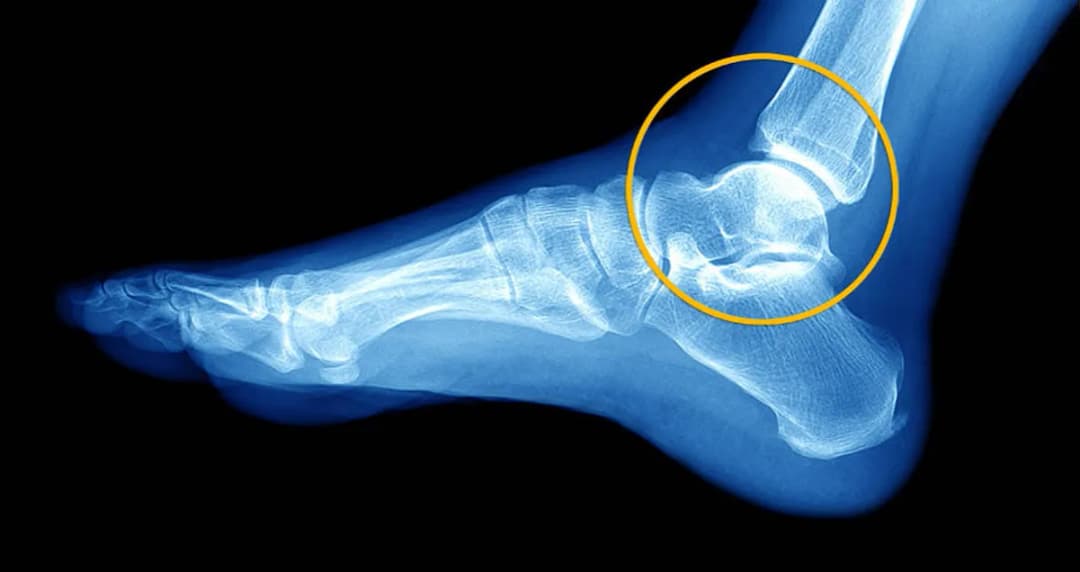

Skręcenie stawu? Zrozum objawy, stopnie urazu i protokół PRICE. Dowiedz się, kiedy iść do lekarza oraz jak skutecznie leczyć i zapobiegać nawrotom!

Poznaj objawy skręcenia stawu biodrowego: ból, obrzęk, ograniczenie ruchu. Dowiedz się, jak odróżnić je od złamania i zwichnięcia. Sprawdź, jak udzielić pierwszej pomocy i skutecznie leczyć uraz.